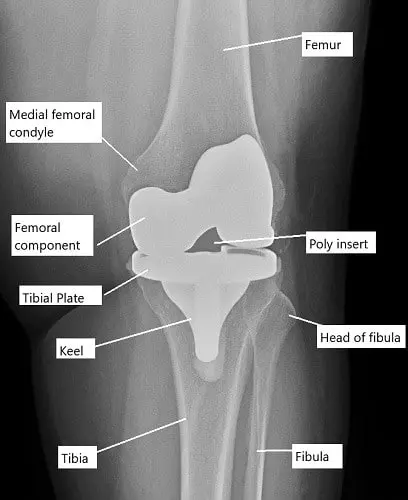

The knee joint is a hinge joint formed by the femur (thigh bone), tibia (shin bone), and patella (kneecap). The femur and tibia are covered with articular cartilage to allow smooth movement, and the patella glides over the femoral surface. Knee replacement surgery involves removing the damaged portions of these bones and replacing them with prosthetic components. These prosthetic components are either fixed with bone cement (cemented) or press-fitted into the bone (cementless), and they restore the function and mobility of the knee joint.

X-ray showing total knee replacement.

- Femoral Periprosthetic Fractures: These fractures occur in the femur, either above or below the femoral component. They are more common during or immediately after surgery.

- Tibial Periprosthetic Fractures: These occur in the tibia, often as a result of misalignment or pre-existing bone weakness.

- Patellar Periprosthetic Fractures: These fractures happen in the patella, often due to intraoperative injury or issues with patella resurfacing.

Femoral periprosthetic fractures

The fracture inner side of the lower end of the femur (medial femoral condyle) occurs mostly during the surgery. The management of femur periprosthetic fractures depends upon the location of the fracture and the stability of the prosthesis.